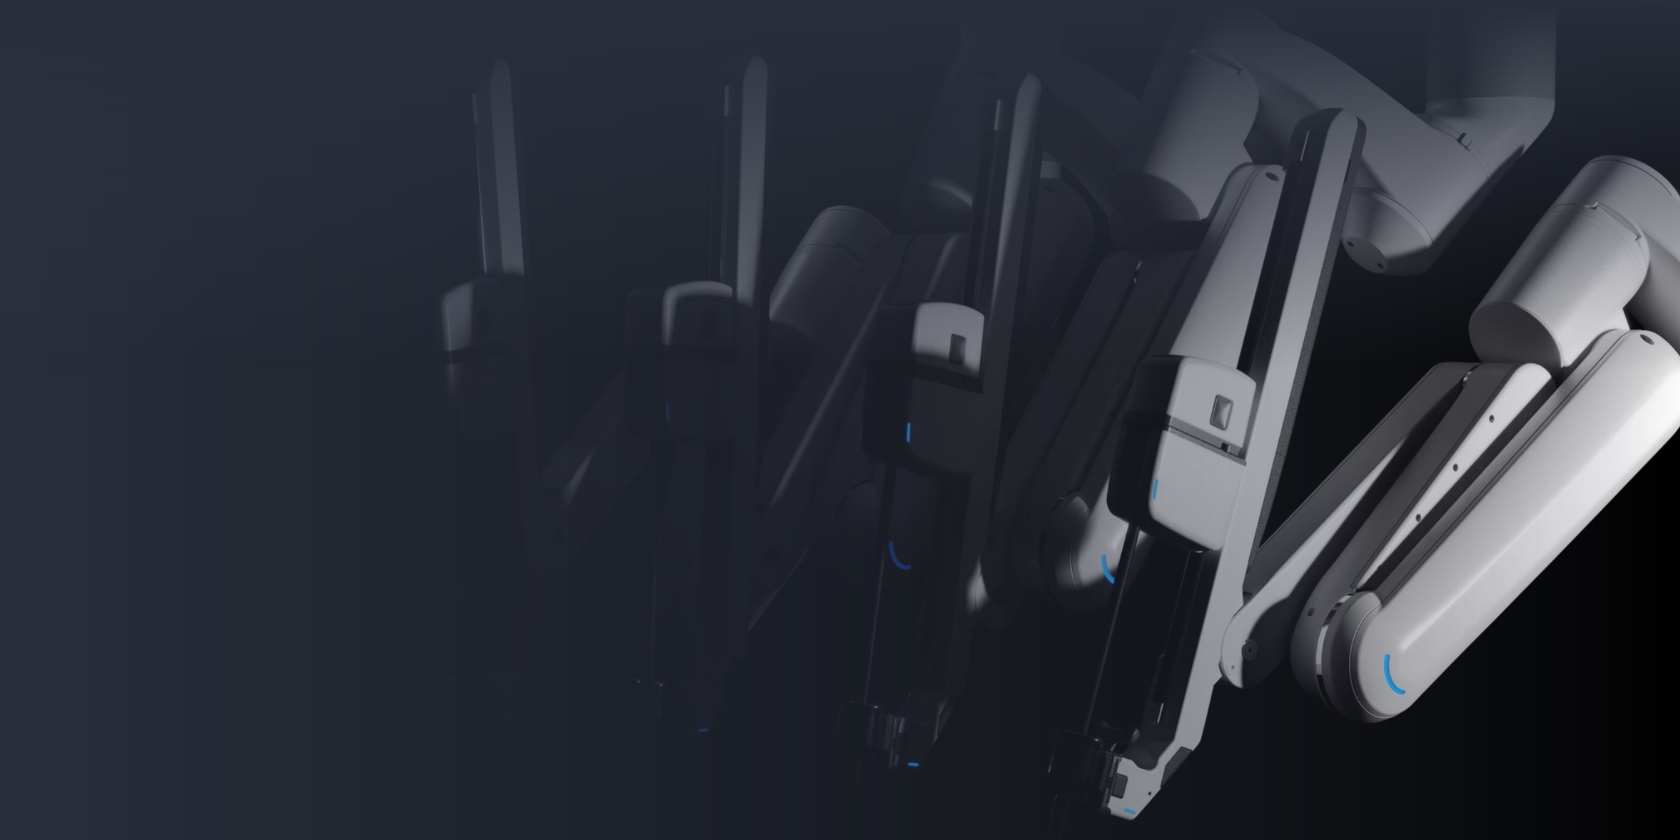

A Full Range of Urology Care

Our Urologic Specialties

Find My Condition

Urologic conditions include can affect the prostate, kidneys, bladder and urinary tract. Find your condition, and get exceptional urologic care.